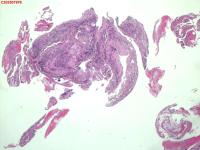

右肺上叶开口处 气管镜咬检

性别

男

年龄

65岁

临床诊断

一般病史

肺TB

标本名称

大体所见

右肺上叶开口上缘处可见肉芽增生,予咬检。

感觉:炎性纤维组织增生